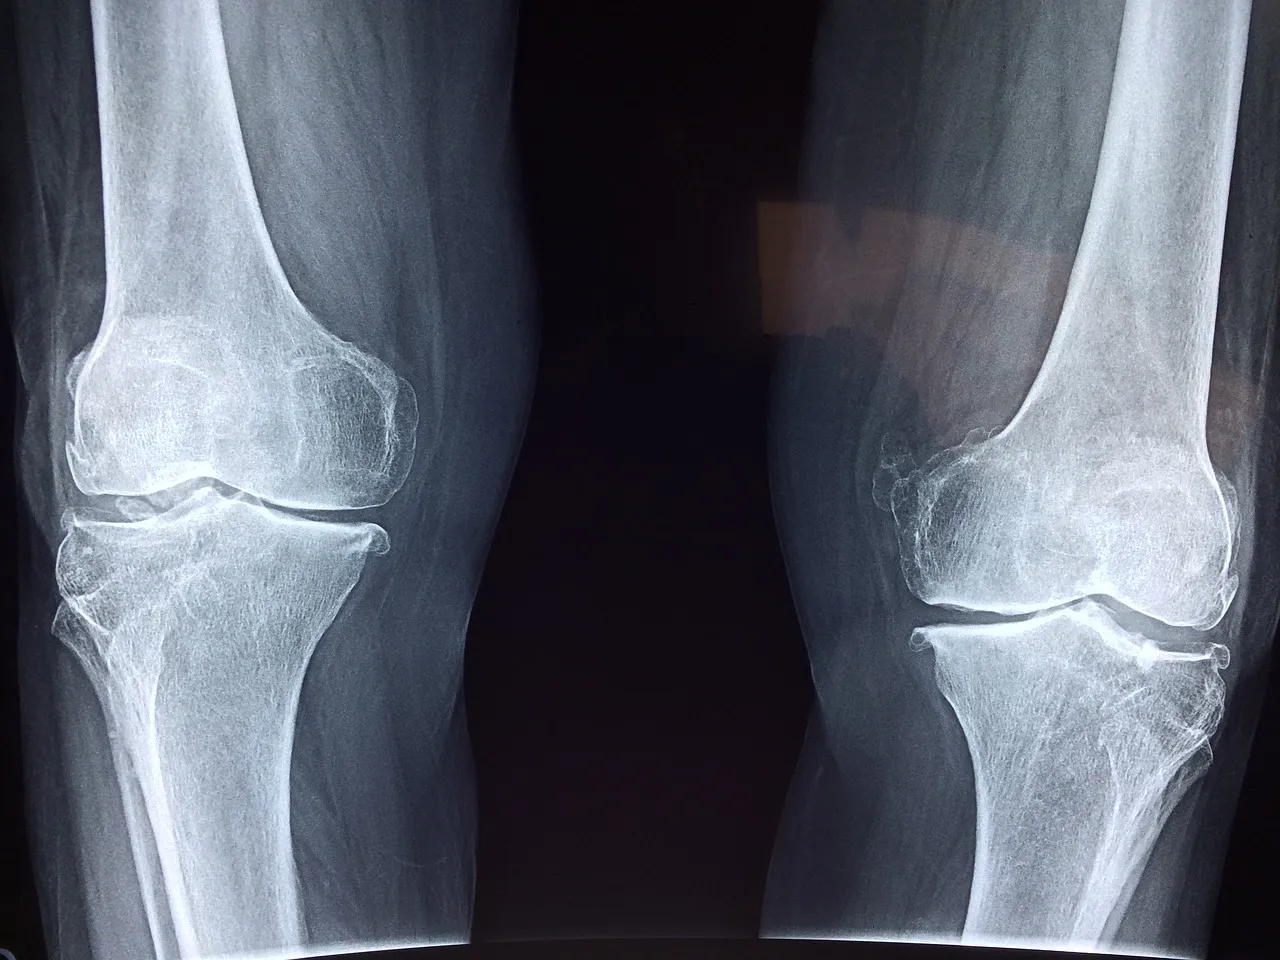

콘드로이친은 특히 골관절염의 증상을 완화하는 데 도움이 됩니다. 연골의 여러 구성 요소의 합성을 증가시키고 연골의 분해를 방지하여 통증을 완화합니다. 특히 무릎 통증에 효과가 있다고 알려져 있습니다. 여러 연구에서 콘드로이친 복용이 통증을 약 20% 감소시킨다고 보고되었습니다. 또한, 연골을 보호하고 재생하는 데도 효과가 있습니다.